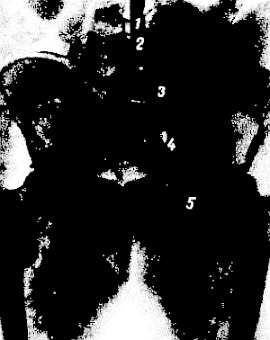

С помощью инъекции контрастного вещества в брюшную часть аорты (аортография; рис. 248) получается изображение брюшной части аорты, pars abdominális aórtae. Видны также бифуркация ее и ход обеих общих подвздошных артерий и их крупных ветвей. На живом вследствие прижизненного тонуса и подвижности соседних органов брюшная часть аорты может несколько смещаться вправо и идти слегка дугообразно выпуклостью вправо, что может ошибочно быть принято за патологию, например оттеснение аорты опухолью.

Рис. 248. Аортография на живом человеке (по Ю. С. Петросяну).

1 - аорта; 2 - бифуркация аорты; 3 - общая подвздошная артерия; 4 - наружная подвздошная артерия; 5 - бедренная артерия.